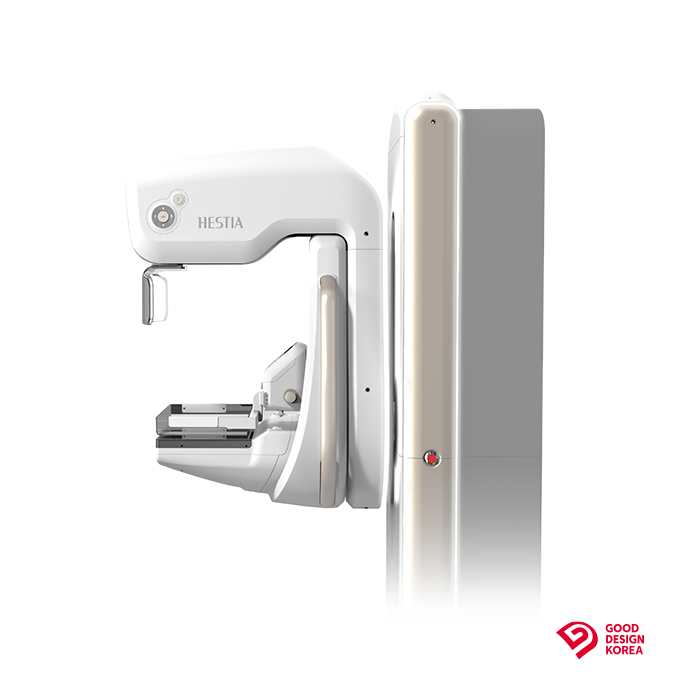

Zmienna projekcja

System pozycji izocentrycznej wraz z obrotowym ramieniem typu C umożliwia szybką zmianę projekcji bez konieczności przestawiania pacjentki, gwarantując powtarzalność przy rozbudowanym protokole badania.

Detektor cyfrowy FFDM

Nowoczesny detektor cyfrowy o wysokiej czułości i rozdzielczości, zapewnia precyzyjne odwzorowanie detali anatomicznych, w tym mikrozwapnień i zmian strukturalnych miąższu.

Inteligentna kompresja

System automatycznego doboru siły kompresji uwzględnia budowę anatomiczną pacjentki oraz opór tkanek, zapewniając optymalne warunki obrazowania przy jednoczesnym zwiększeniu komfortu pacjentki.

Tomosynteza 3D

Hestia została zaprojektowana jako system modułowy, który umożliwia rozbudowę o tomosyntezę piersi – warstwowe obrazowanie 3D, zwiększające wykrywalność zmian.